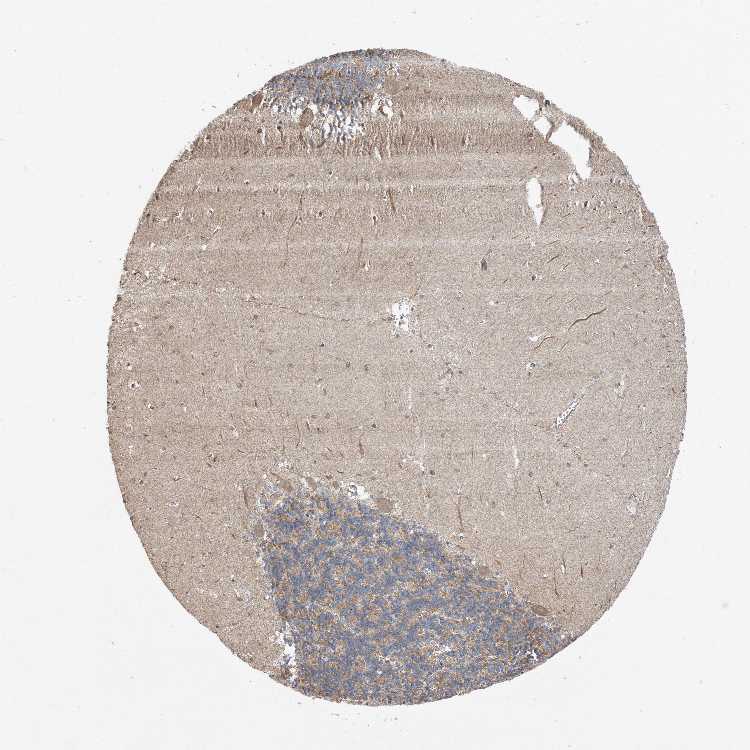

CEREBELLUM - Antibody stainingi

Antibody staining in the annotated cell types in the current human tissue is reported as not detected, low, medium, or high, based on conventional immunohistochemistry profiling in selected tissues. This score is based on the combination of the staining intensity and fraction of stained cells.

Each image is clickable and will lead to virtual microscopy that enables deeper exploration of all samples and also displays staining intensity scores, fraction scores and subcellular localization as well as patient and tissue information for each sample.

Antibody HPA035862

Purkinje cells Medium

Cells in granular layer Medium

Cells in molecular layer Low